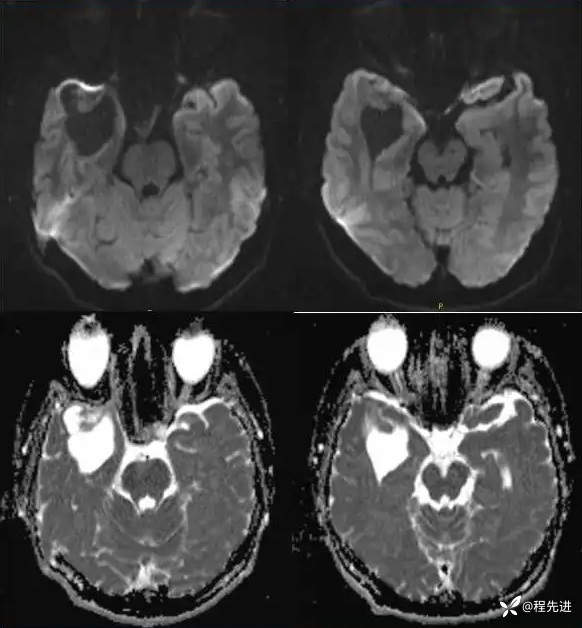

DWI、ADC: